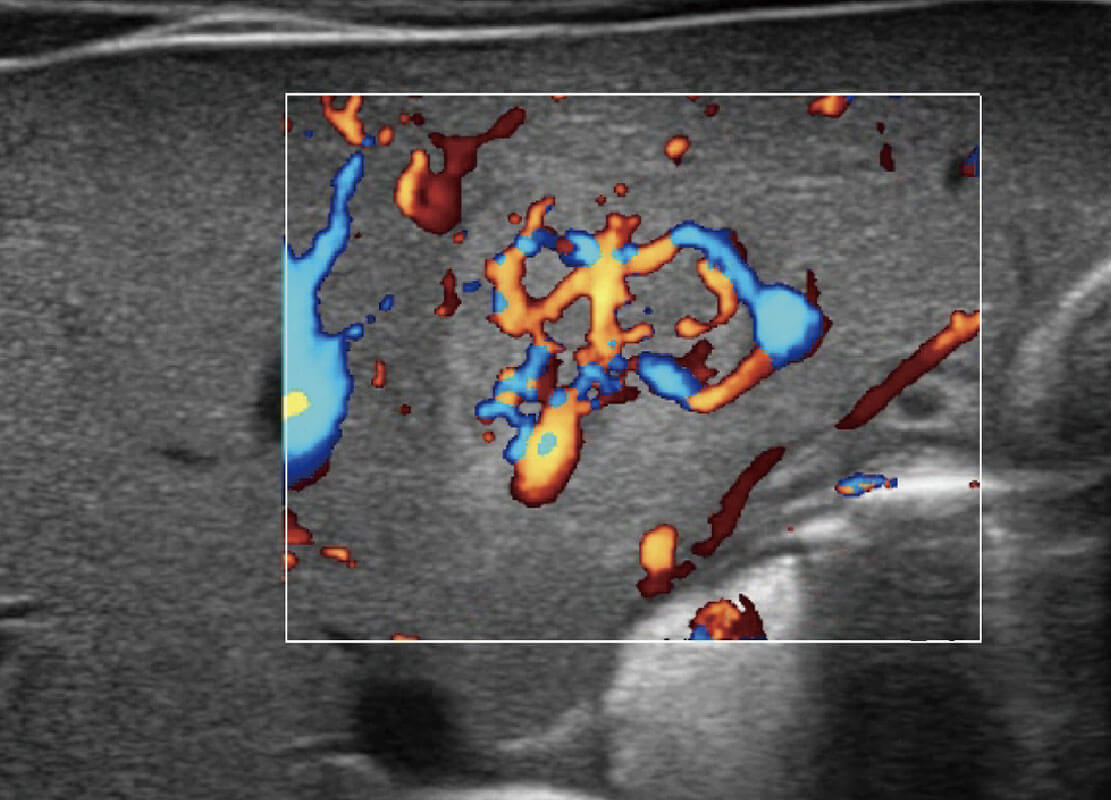

P60搭载宽频带线阵探头、宽景成像、弹性成像技术,为您提供乳腺应用方案。P60支持高频相控阵探头、线阵探头、腹部高频探头、腹部微凸探头等,丰富的探头群搭载敏感的彩色血流成像,适用于新生儿多种脏器检测要求,满足新生儿筛查需求。

乳腺导管癌

乳腺癌显微血流

新生儿肝血管癌